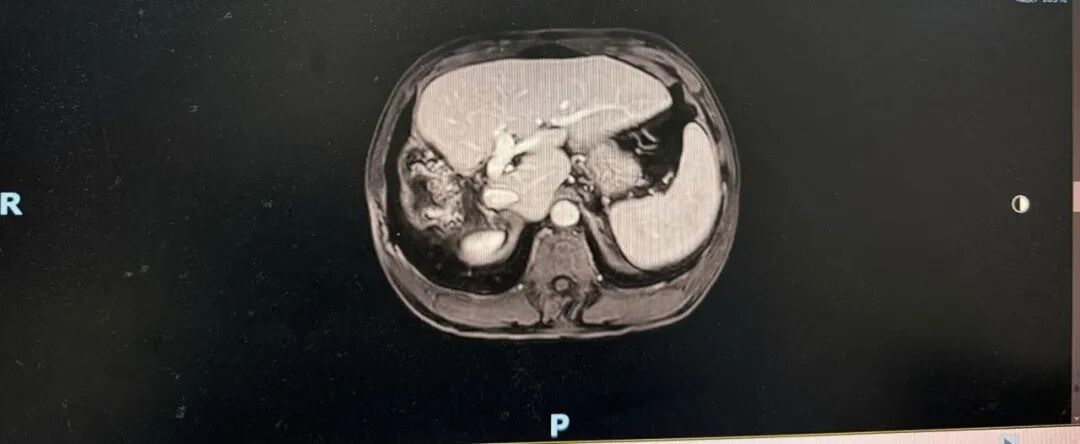

➣ 2019年4月23日,腹部增强CT:右肝巨块型肿块,大小约16*15*10cm,伴周围子灶形成;右肝静脉、门静脉右后支受侵;肿块体积 1236.63㎝³,左肝体积 863.97㎝³。

疗效评价1

mRECIST评价标准:PR

➣ 目标病灶(动脉期增强显影)的直径总和缩小>30%

肿瘤体积明显缩小:749.25⁄1236.63 cm³ ≈60%

➣ 病灶及受累血管仍局限在右半肝,且病灶缩小;安全性:Child-Pugh A级;剩余肝体积 / 标准肝体积 > 40%;ICG 15分钟滞留率=6.4%,手术切除可行。